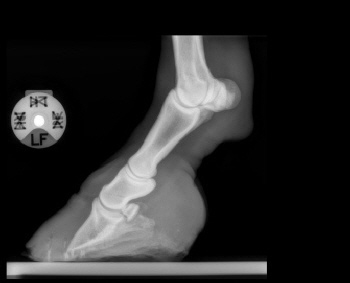

Röntgenbilder akuter- und chronischer Hufrehehufe vorher und nachher

Nachstehend stellen wir einige Röntgenbilder von Hufrehepferden ins Netz, welche das Vorher und das Nachher zeigen. Wir möchten damit aufzeigen, dass durch eine richtige Hufbearbeitung ein Hufbein wieder in eine korrekte Lage innerhalb der Hornkapsel zu liegen kommen kann.

In besonders schweren Fällen wurde doch zumindest eine Optimierung angestrebt.

nachher